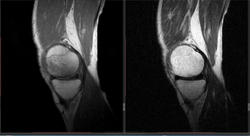

Мужчина 1963 г.р. Жалуется на боль в левом коленном суставе около 6 мес, в последний месяц стало совсем тяжко. Со слов заболел зимой, когда во время прогулки коленки сильно замерзли. Сам думаю на асептический некроз, но смущает множественность поражения.

Дмитрий, я в заболеваниях суставов не дока, но трабекулярный отек вкупе с выпотом может быть обусловлен воспалительными изменениями , но полностью начальные проявления аваскулярного некроза не могу отрицать.

я бы не поставил аваскулярный некроз. если исключена травма, дифференцировать с артритом.

Хрящ не поврежден, для артрита...